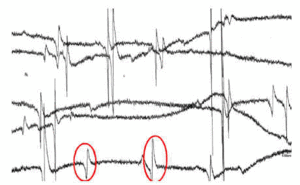

Paciente de 72 años de edad ingresado en Unidad de Cuidados Intensivos (UCI) con insuficiencia respiratoria global por una reagudización de enfermedad pulmonar obstructiva (EPOC). El paciente tiene dificultades para la desconexión de la ventilación mecánica por atelectasias de repetición y acidosis respiratoria grave. En la figura 1 se observa la radiografía de tórax en ventilación mecánica y en la figura 2 una de la imágenes de atelectasia al reducir el soporte ventilatorio. Se realizó electromiograma de diafragma mediante punción del pilar anterior por acceso retroesternal, en el que aparecieron datos de denervación (fibrilaciones y ondas rítmicas de denervación "marcadas con un circulo rojo") (fig. 3). El paciente fue dado de alta de UCI y del hospital con soporte ventilatorio parcial.

Figura 1.